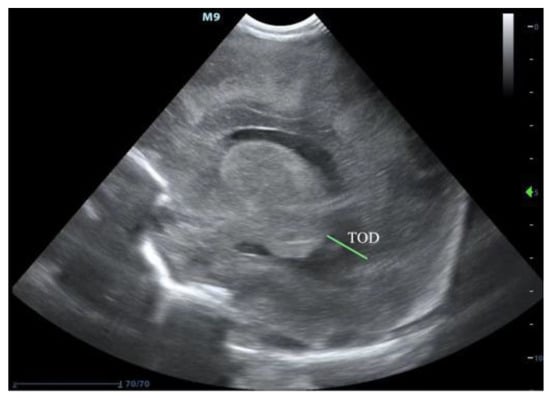

2. Ultrasound Diagnosis of PHVD